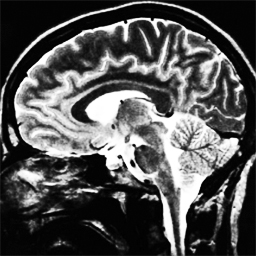

In Figure 1.1 the influence of the choice of a constant in (1.1) is shown, over-regularising the reconstructed image if chosen too small and under-regularising if chosen too large. Moreover, in Figure 1.2 the reconstructed images with constant and spatially-dependent are shown, where has been optimized with the bilevel approach for (1.1) proposed in [9].

4.1. Uniform Gaussian noise

In this first experiment, we consider the denoising problem with brain scan images. The first set consists of images of pixels and Gaussian noise with zero mean and variance . The original and noisy images are shown in Figure 4.1. The domain decomposition-semismooth Newton algorithms run with the parameter values , , and . The results are shown in Figure 4.2. From the surface representation of , we can observe that is continuous and its shape is related to the one of the original image. In particular, the regularization is stronger in homogeneous regions in the image, and weaker where the image intensity undergoes variations on a smaller scale.